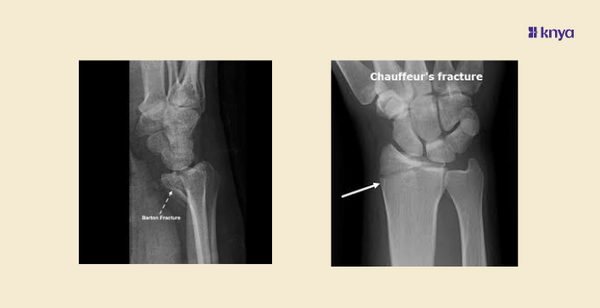

What is Barton Fracture?

A Barton fracture is an intra-articular fracture of the distal radius characterized by a fracture-dislocation of the radiocarpal joint. It was first described by John Rhea Barton in 1838. Barton fractures are classified into two types: dorsal and volar, depending on the direction of the displacement.

Dorsal Barton Fracture

ย Involves a dorsal displacement of the carpus along with a dorsal rim fracture of the distal radius.

Volar Barton Fracture

Involves a volar displacement of the carpus along with a volar rim fracture of the distal radius.

Diagnosis

Diagnosis is made through clinical examination and imaging studies.ย

- X-rays are the primary imaging modality, revealing the fracture and the direction of displacement

- CT scans can provide additional detail in complex cases.